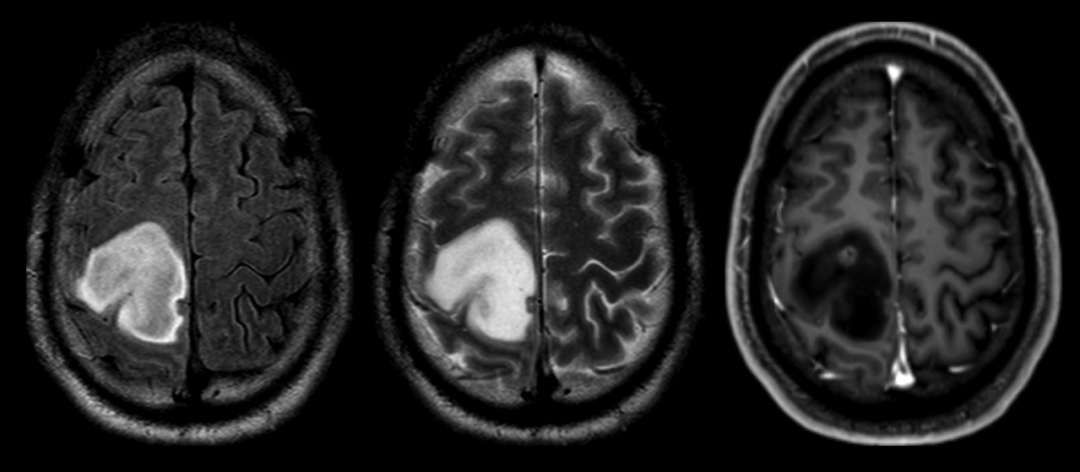

肿瘤显示 T2-FLAIR 错配征,尽管存在个小结节增强,但术后病理证实为 IDH 突变的胶质母细胞瘤

4 例 T2-FLAIR 错配,但是年龄 ≤18 岁,a = 2 岁(毛细胞星形细胞瘤),b = 12 岁(病理提示灰质异位,随访 1.5 年时无进展/复发的证据),c = 14 岁(H3K27M 改变型中线胶质瘤),d = 18 岁(儿童低级别弥漫星形细胞瘤,MYB 改变)。